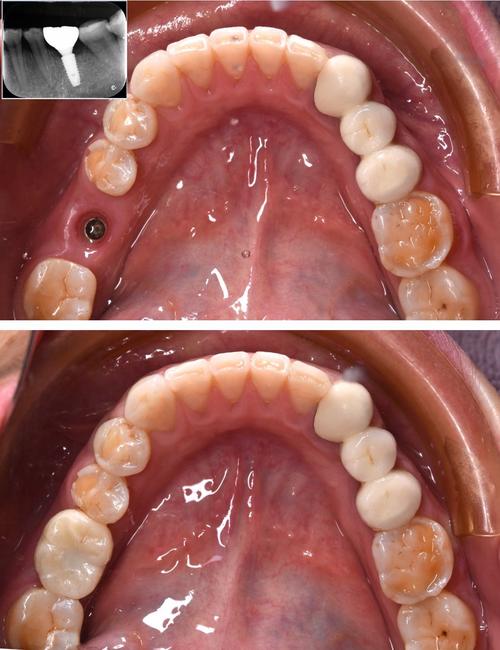

- 术前评估:拍摄CBCT(锥形束CT)三维重建牙槽骨,明确血管位置、走行及骨内分支情况;详细询问病史,筛查高血压、糖尿病、凝血功能障碍及抗凝药物使用史,必要时停用抗凝药5-7天并监测凝血功能;控制血压<140/90mmHg,血糖<8mmol/L。